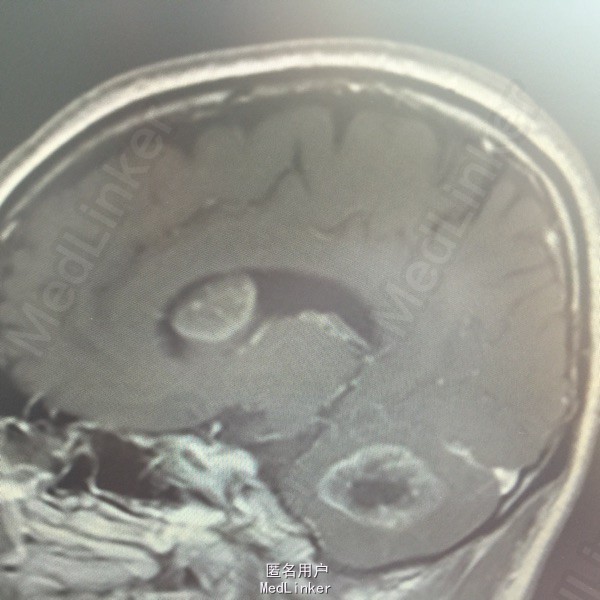

男,54岁,以头痛半个月入院。 现病史:半个月前无诱因头痛,呈胀痛,无呕吐,无意识障碍,病来咳嗽、咳痰,体重减轻约5斤,无发热。 既往史:无特殊。

查体:BP:150/100mmHg,神清语明,两瞳孔等大正圆,直径约3.0mm,光敏,四肢肌力5级,肌张力正常,腱反射艹,左侧共济运动阳性,病理征阳性,脑膜刺激征(-)。 辅查:见下:

肺癌脑转移。 影像解读(影像如何解读是临床工作中非常重要的一环)。 左侧额叶近皮质长Tl长T2信号,局部颅骨缺损,右侧枕叶不规则病灶,TlWl呈中心呈等信号,周围高信号,T2Wl呈高低混杂信号,伴大片水肿,相邻侧脑室后角、胼胝体受压。增强呈不规则环环强化。 已进行局部放疗治疗。